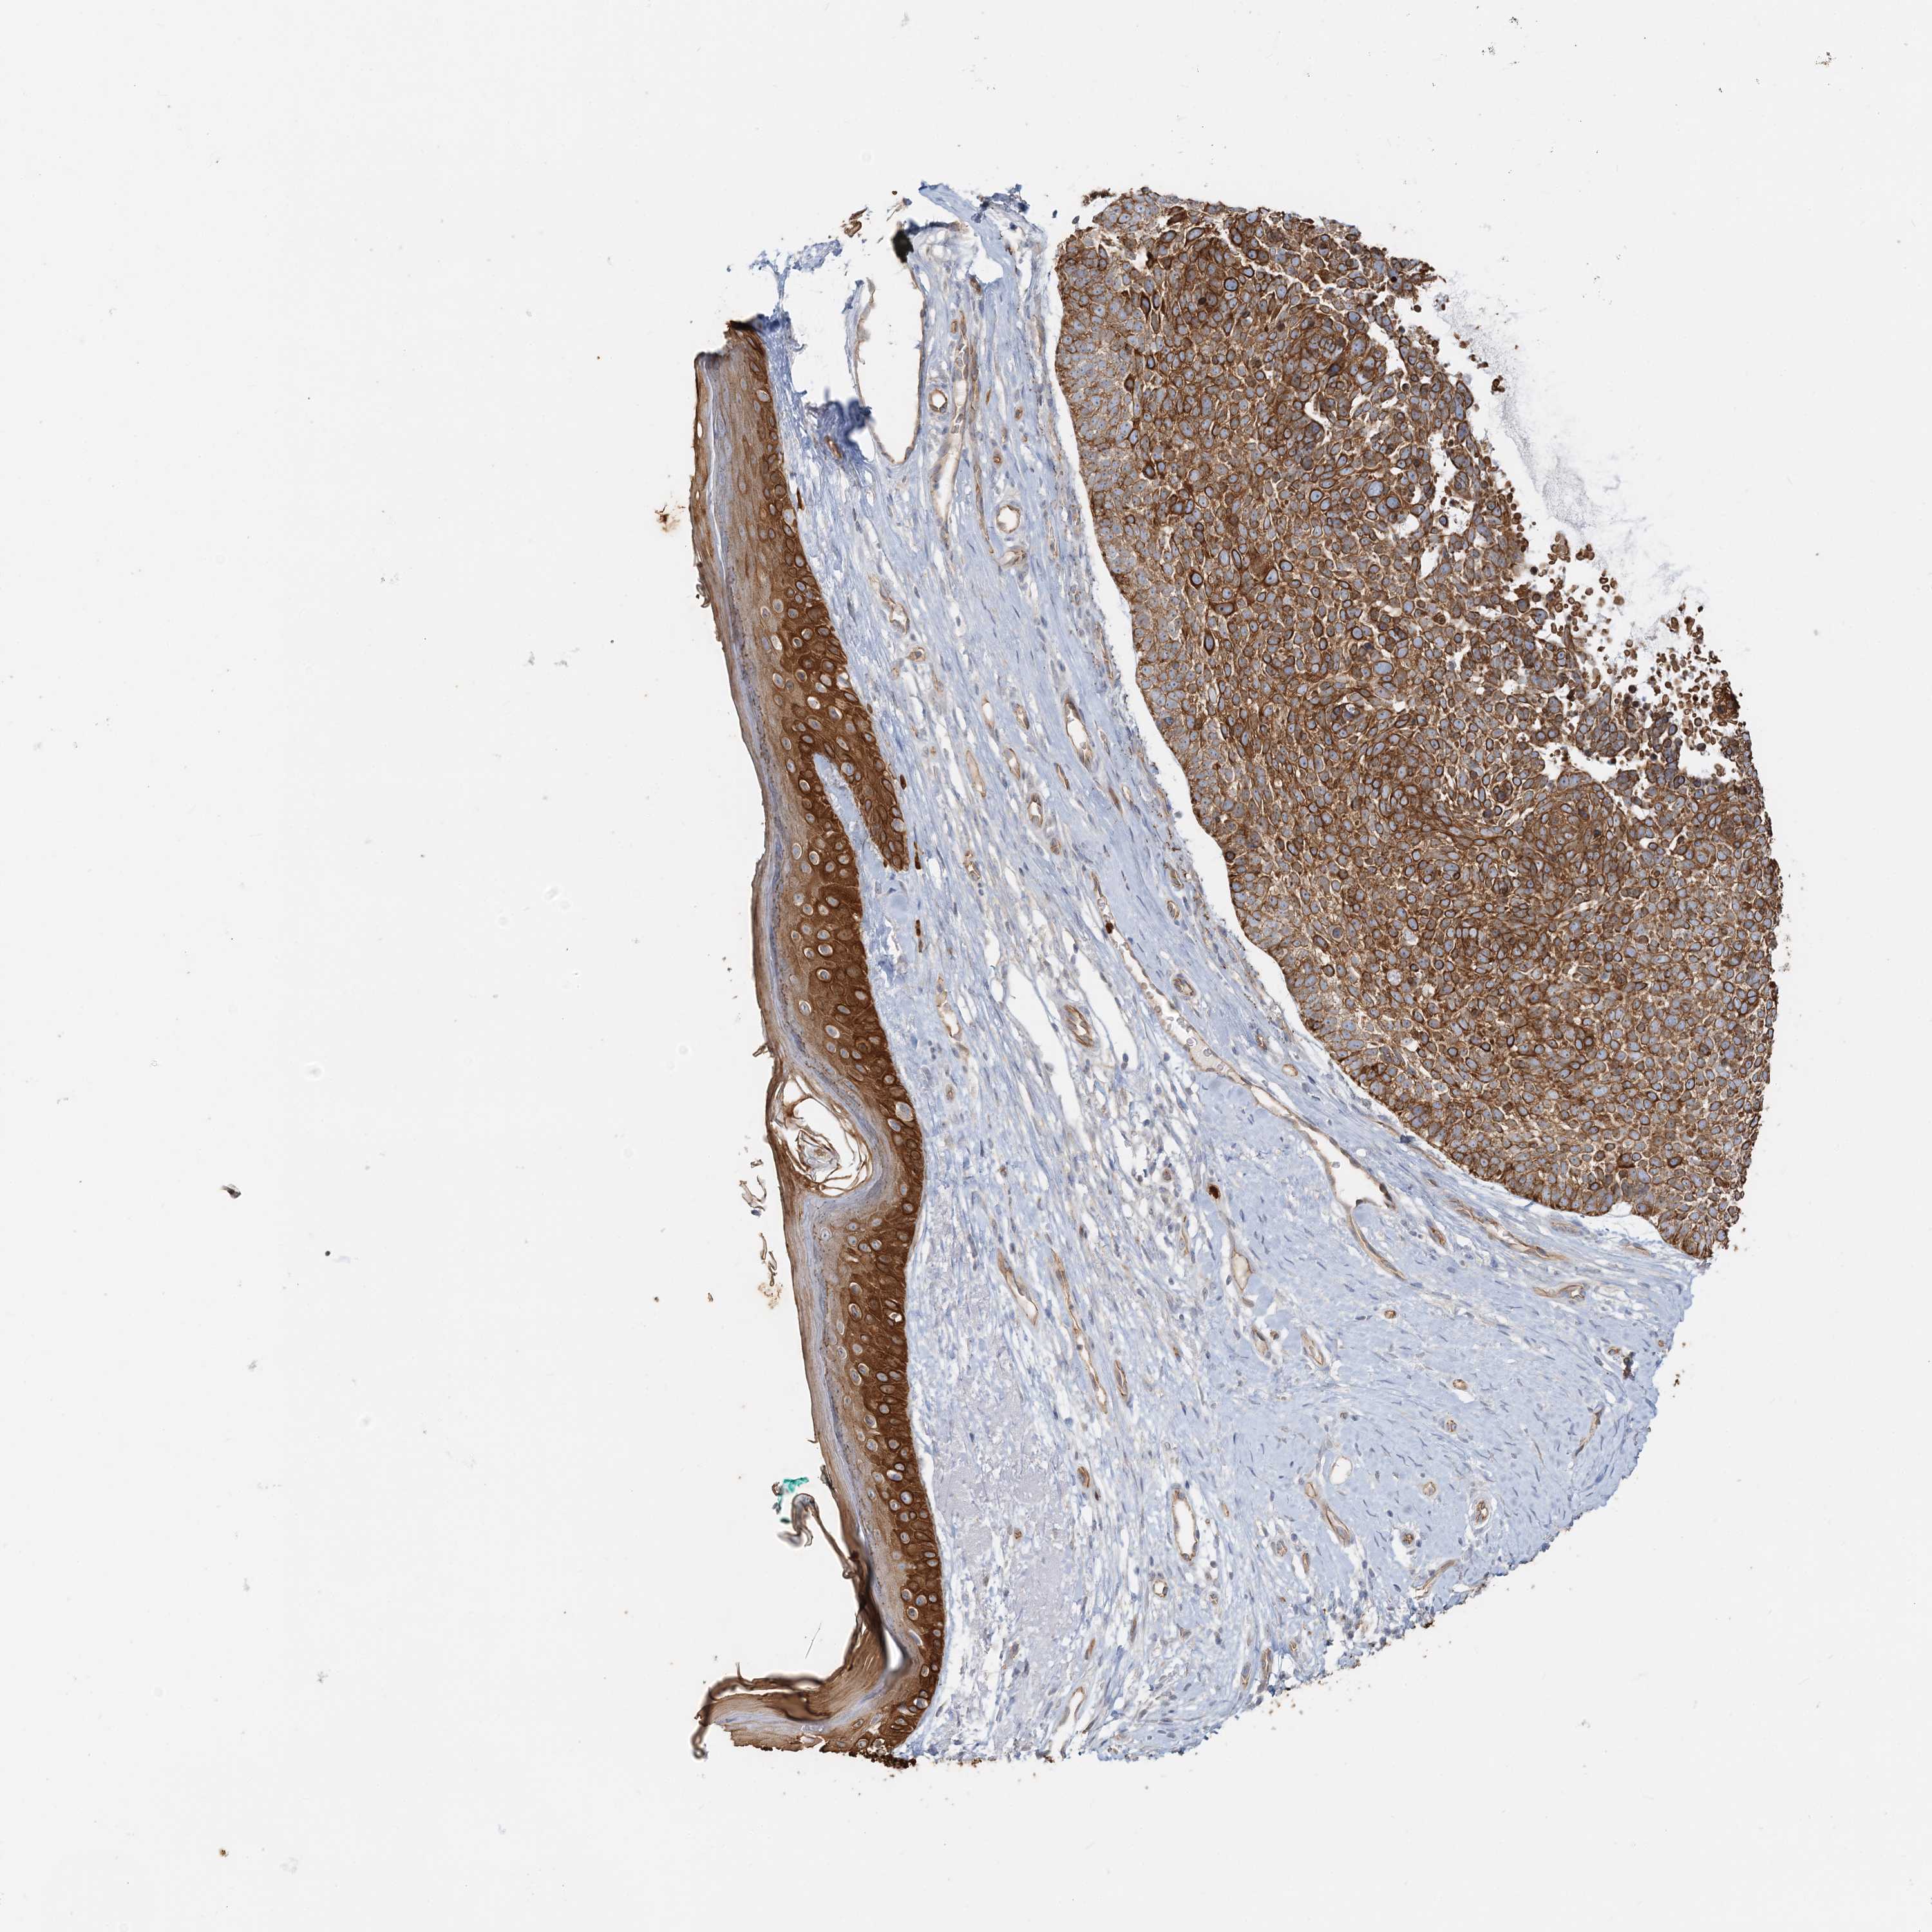

Basal cell and squamous cell cancer

SKIN CANCER - Protein expressioni

A mouse-over function shows sample information and annotation data. Click on an image to view it in a full screen mode. Samples can be filtered based on level of antibody staining by selecting one or several of the following categories: high, medium, low and not detected. The assay and annotation is described here.

Antibody stainingi

Antibody staining in the annotated cell types in the current human tissue is reported as not detected, low, medium, or high, based on conventional immunohistochemistry profiling in selected tissues. This score is based on the combination of the staining intensity and fraction of stained cells.

Each image is clickable and will lead to virtual microscopy that enables deeper exploration of all samples and also displays staining intensity scores, fraction scores and subcellular localization as well as patient and tissue information for each sample.

Antibody HPA036805

Antibody HPA036806

Staining

High

Strong

>75%

Cytoplasmic/membranous

Squamous cell carcinoma, NOS